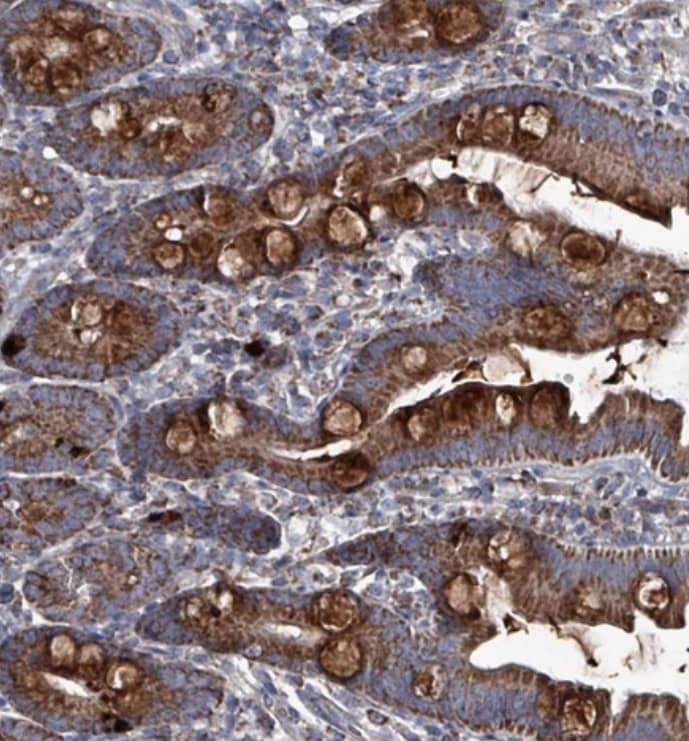

Immunohistochemistry-Paraffin: ABHD18 Antibody [NBP2-30555] - Staining of human kidney shows strong cytoplasmic positivity in cells in tubules.

Staining of human small intestine shows strong cytoplasmic positivity in goblet cells.